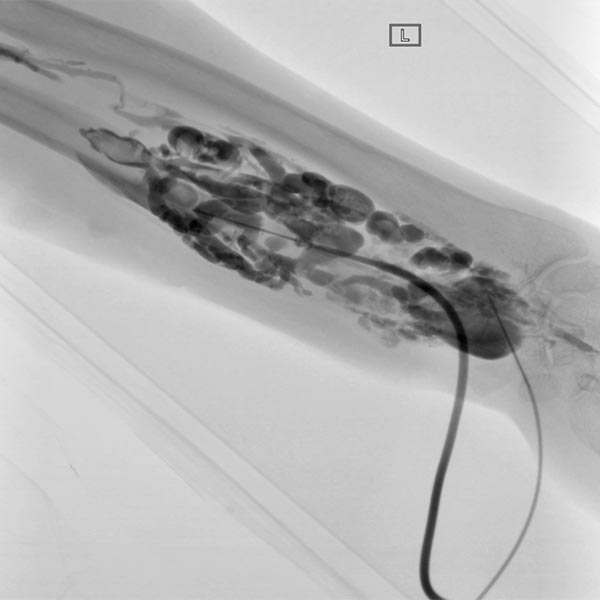

Es erfolgten insgesamt sieben Sitzungen einer Sklerosierungstherapie, in denen die perfundierten Anteile der venösen Malformation mittels Polidocanol 3 % sklerosiert wurden (bis zu 4 ml pro Sitzung). Dabei werden die perfundierten Anteile der Malformation mit einer 21G-Nadel direkt punktiert. Nach Aspiration von venösem Blut erfolgt die Kontrastmittelinjektion zur Beurteilung der Verteilung, respektive der Kommunikationen der einzelnen Malformationsanteile mit Drainagevenen. Anschließend erfolgt die langsame Injektion des aufgeschäumten Polidocanols, gefolgt von einem elastischen Kompressionsverband für 24 h.